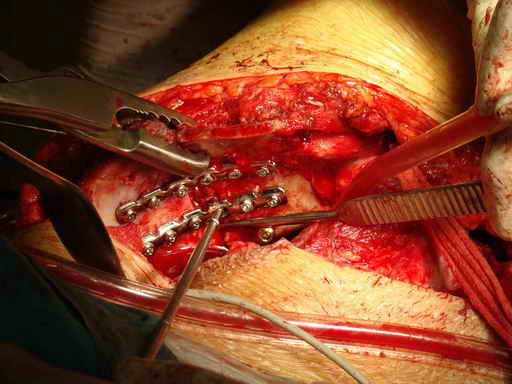

Укладка тазовой пластины "matta"

Операционная. Оперирует д.м.н. проф. Казанцев А.Б.